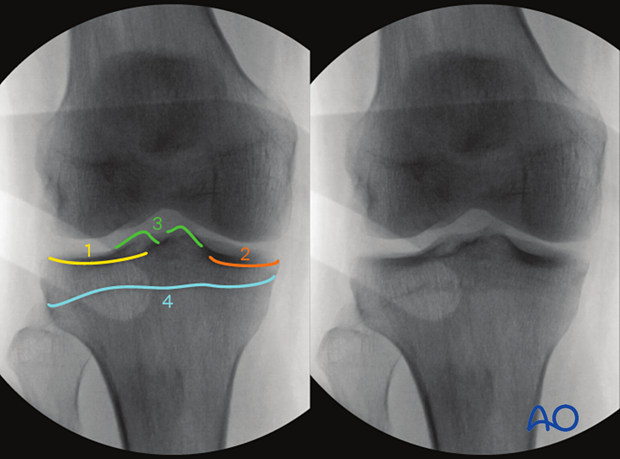

Intraoperative imaging of the proximal tibia